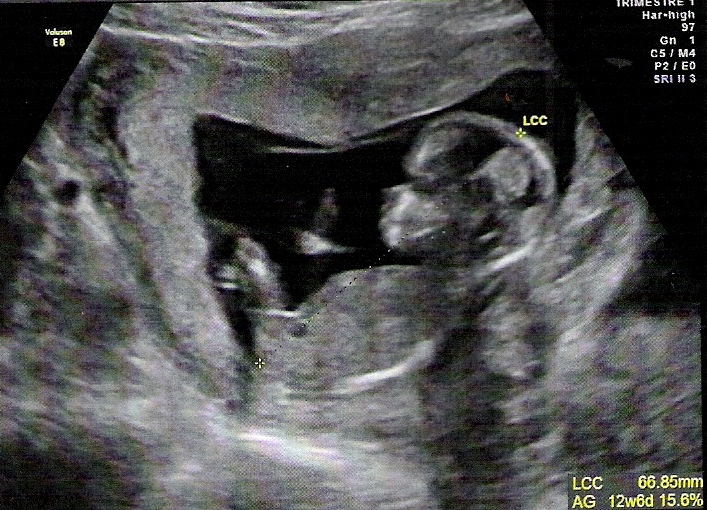

echo grossesse